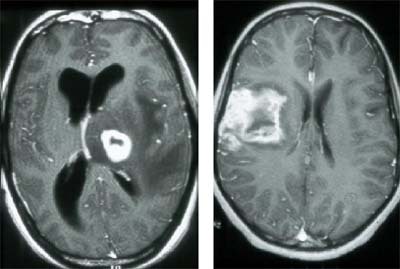

Toxoplasmosis is a protozoal intracellular parasite, which is probably the most common opportunisitic infection seen in AIDS patients. It is especially important to identify toxoplasmosis, because it responds well to treatment. CT and MR can be nonspecific, but the radiologist can sometimes find a telltale rim-enhancing abscess, particularly in the basal ganglia, and with cortical involvement.

| Toxoplasmosis infection in the brain of an HIV patient. Images courtesy of Dr. Peter Corr. |